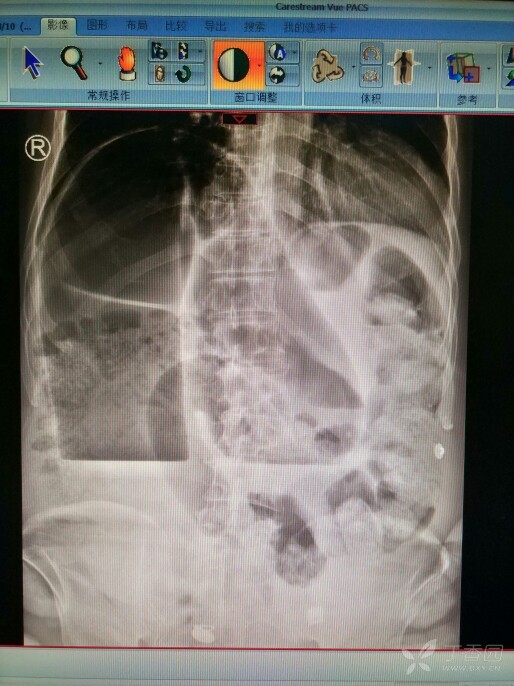

请帮我看看立位腹部平片是啥问题

图片尺寸768x1024